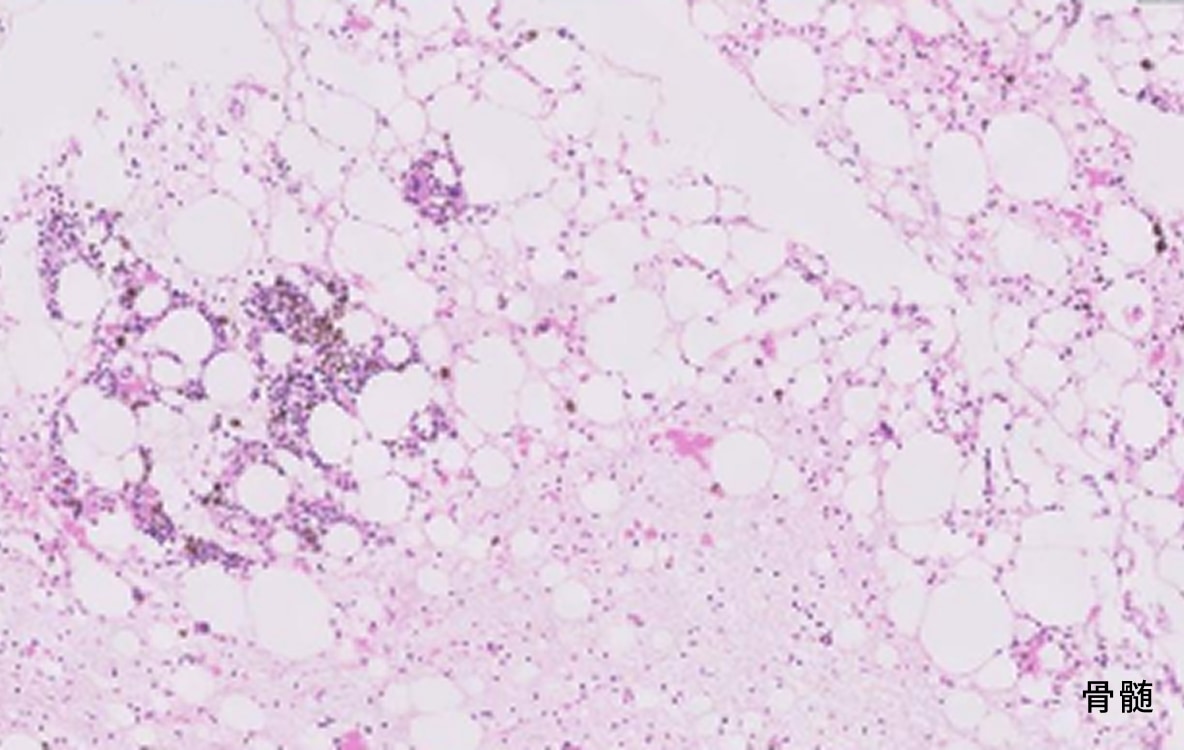

血液疾患の原因は複雑でその背景や原因に別の病気があることも少なくありません。そのため血液検査のみならず、レントゲン(X線)や超音波(エコー)などにより腫瘍や体の中の出血の有無をチェックしたり、鎮静/全身麻酔下での骨髄検査にて骨髄の異常の有無を確認し原因を追究します。